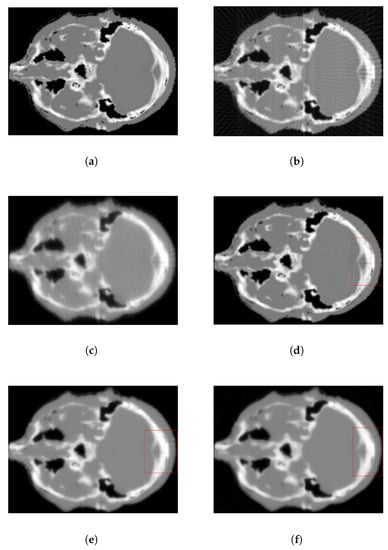

The digital brain phantom, widely employed for evaluating CBCT reconstruction, was used for validation. We sampled 90 projection images using the forward method through the TIGRE Toolkit and added noise with a level of . The original digital brain slice served as a benchmark for CBCT reconstruction. Additionally, four classical methods discussed in the introduction—FDK, OS-SART, ASD-POCS, and ordered subset ASD-POCS (OS-ASD-POCS)—were used for comparison.

Reconstruction results are displayed in Figure 2, with the 160th slice in the sagittal (Y-axis) direction chosen for comparison due to its information richness. FDK, proposed for full-view reconstruction, produces an acceptable image from sufficient projection data but suffers from severe streak artifacts in Figure 2b when projection data are insufficient. Streak artifacts are still apparent in Figure 2c for OS-SART but are significantly reduced compared to FDK. Edges appear blurred and some critical structural details are lost in Figure 2d,e, despite ASD-POCS’s ability to remove artifacts and suppress noise. For a clearer comparison, the region of interest (ROI) marked by the red box in Figure 2d,e is magnified and displayed in Figure 3. The noise reduction effect of the proposed method outperforms that of the ASD-POCS and OS-ASD-POC algorithms.

Figure 2.

Brain phantom reconstruction (slice 160): (a) ground truth, (b) FDK, (c) OS-SART, (d) ASD-POCS, (e) OS-ASD-POCS, (f) proposed method.

Figure 3.

Zoom in on ROI in Figure 2: (a) ASD-POCS, (b) OS-ASD-POC, (c) proposed method.